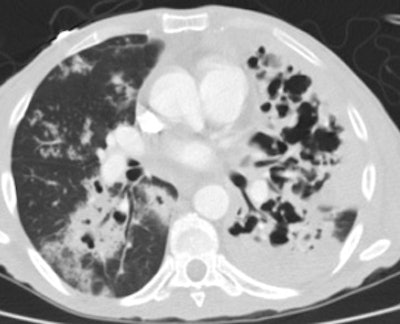

Extensive tuberculosis:

The patient below presented for evaluation of an abnormal CXR. The CT revealed bilateral extensive cavitary consolidations (essentially replacing the left lung), a large cavitary lesion in the right apex, and multiple scattered nodules and "tree-in-bud" opacities. The patient was found to have active TB.